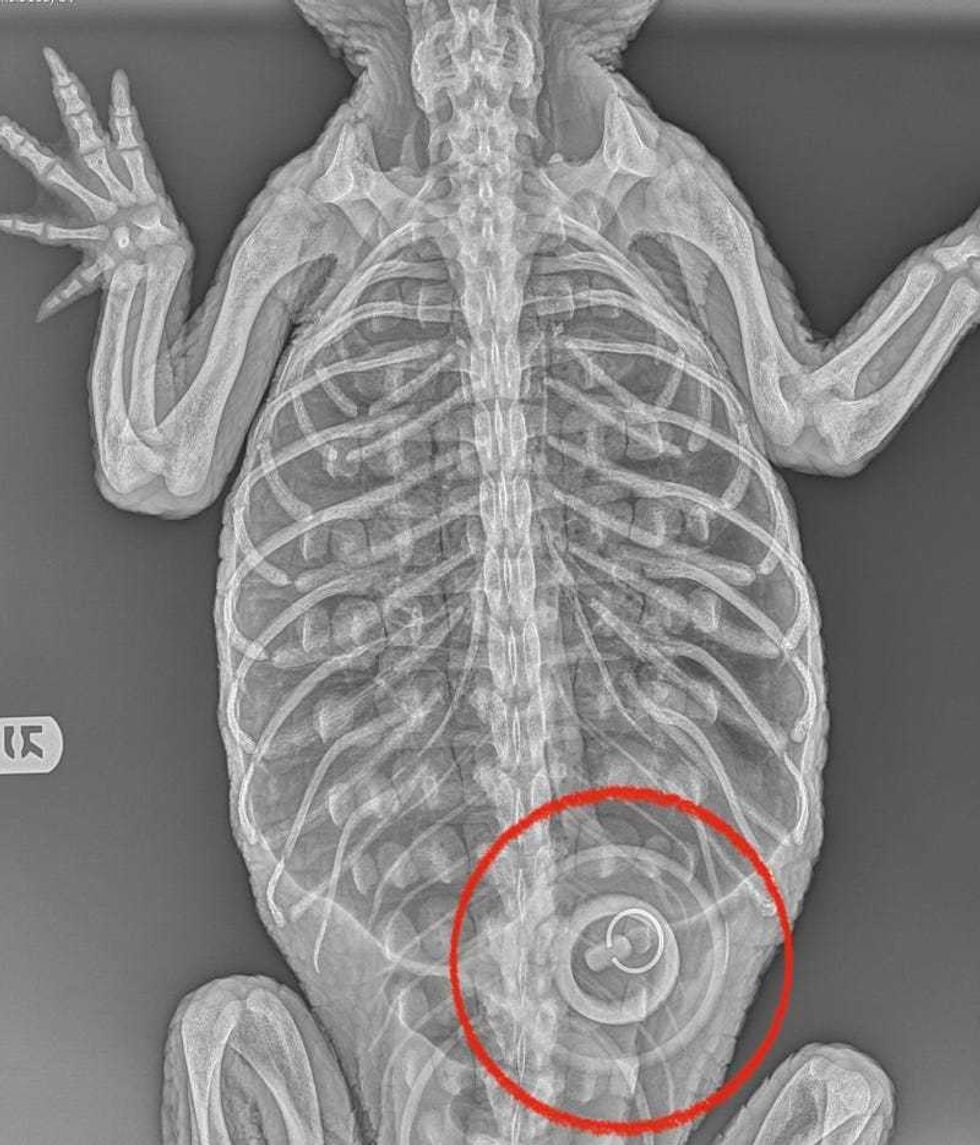

"Despite extensive ongoing medical treatment, nutritional support and the successful removal of a bathtub stopper she had ingested while illegally kept as a pet, the alligator died on Sunday," the Bronx Zoo said in its latest update on the gator.

She also had a chronic ulcer in her stomach caused by a rubber stopper. The zoo has previously surmised the stopper came from a tub the alligator was placed in while being kept as a pet.